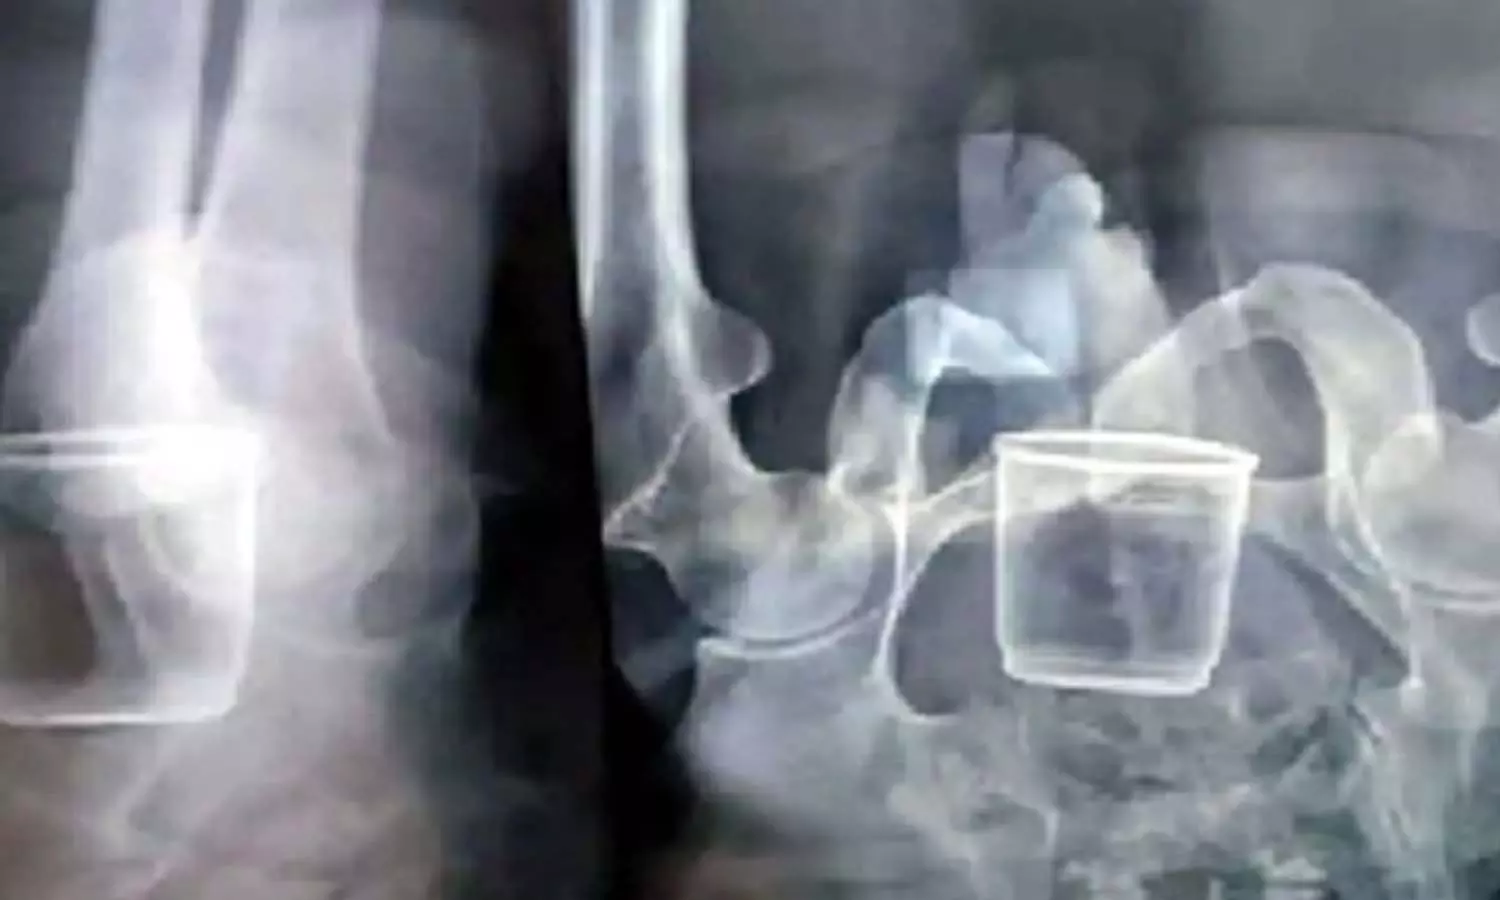

వృద్ధుడి పొట్టలో ఉన్న గ్లాసును చూసి వైద్యులు ఆశ్చర్యపోయారు. మధ్యప్రదేశ్ లోని రాజ్ఘర్ జిల్లాలో ఈ ఘటన జరిగింది. నాలుగు నెలల క్రితం రాందాస్ అమావత్ గ్రామానికి వెళ్లాడు. కారణాలేంటో తెలియదు కాని గ్రామస్థులు అతడిని కొట్టారు. గ్లాసుపై కూర్చోబెట్టి చిత్రహింసలకు గురి చేశాడు. దీంతో ఆ గ్లాసు పొట్లోకి వెళ్లిపోయింది. గ్లాసు పొట్టలోకి వెళ్లిన విషయం బయటకు చెప్పలేక రాందాస్ కొన్ని నెలల పాటు మౌనంగా ఉన్నాడు.

అయితే ఆయనకు కడుపునొప్పి తీవ్రంగా రావడంతో తమ సొంత గ్రామమైన చతుఖేడ్ కు వచ్చి బంధువులకు చెప్పాడు. దీంతో రాందాస్ ను ఆసుపత్రికి తీసుకెళ్లి వైద్య పరీక్షలు చేయించారు. ఎక్స్రే తీయగా రాందాస్ కడుపులో గ్లాస్ ఉండటాన్ని వైద్యులు గమనించారు. అప్పుడు అమావత్ గ్రామ ప్రజలు తనపై దాడి చేసిన విషయాన్ని రాందాస్ చెప్పాడు. ఆపరేషన్ చేసి గ్లాసును తీస్తామని వైద్యులు చెబుతున్నారు.